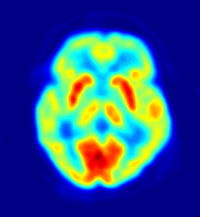

fMRI and PET

Functional magnetic resonance imaging (fMRI) measures changes in blood flow in the brain, but the activity of neurons is not directly measured, nor can it be distinguished whether this activity is inhibitory or excitatory. fMRI is a noninvasive, indirect method for measuring neural activity that is based on BOLD; Blood Oxygen Level Dependent changes. The changes in blood flow that occur in capillary beds in specific regions of the brain are thought to represent various neuronal activities ( metabolism of synaptic reuptake). Similarly, a positron emission tomography (PET), is able to monitor glucose and oxygen metabolism as well as neurotransmitter activity in different areas within the brain which can be correlated to the level of activity in that region.